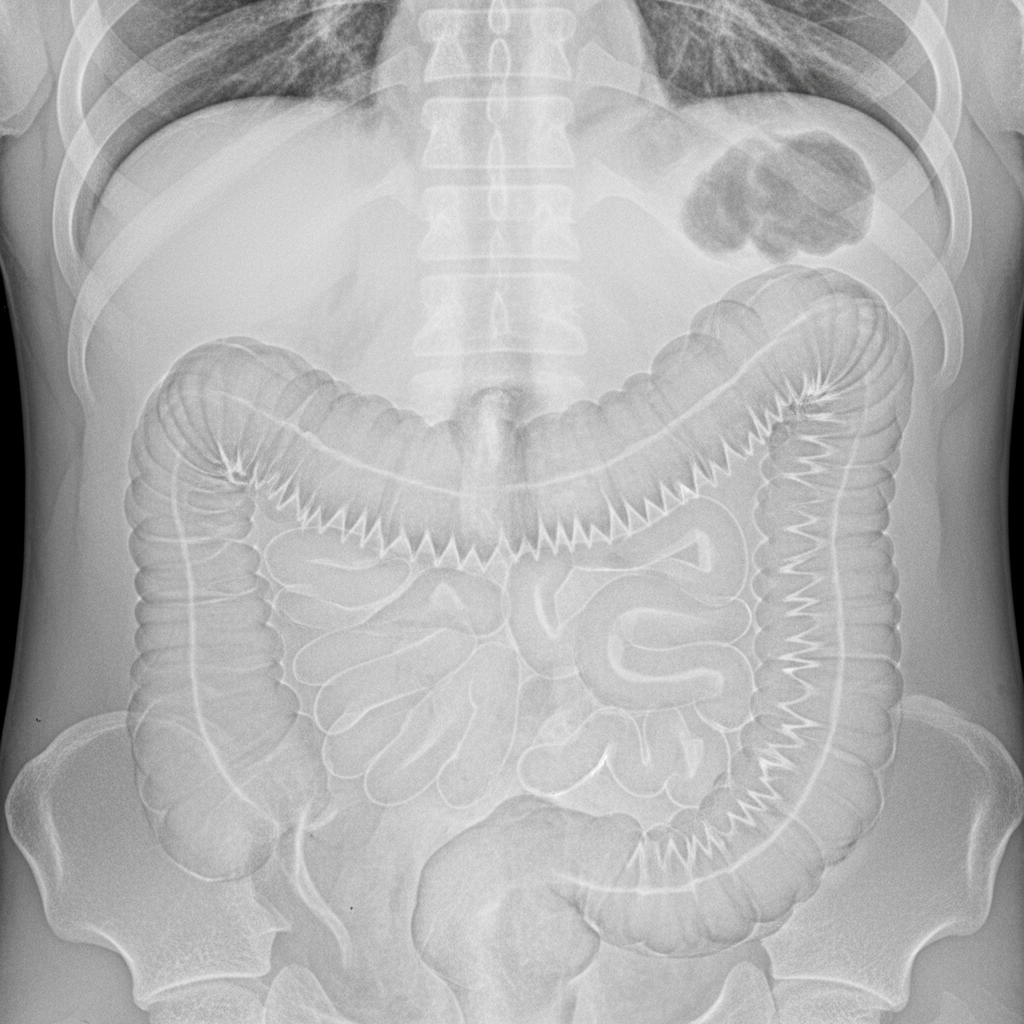

What is the term for the appearance of diverticulosis on a barium enema as depicted in the image?

Explanation: ***Saw tooth appearance*** - Diverticulosis on **barium enema** creates a characteristic **saw tooth pattern** due to **circular muscle hypertrophy** and **spasm** between diverticular outpouchings. - The alternating **indentations** and **bulges** along the colonic wall resemble the teeth of a saw, making this the classic radiological sign. *Cork screw appearance* - This describes the radiological appearance of **diffuse esophageal spasm** on barium swallow, not colonic diverticulosis. - Characterized by **tertiary contractions** creating a **corkscrew pattern** in the esophagus during swallowing. *Bird of prey appearance* - This sign is associated with **sigmoid volvulus** on plain abdominal X-ray, showing a **coffee bean sign**. - The **twisted sigmoid colon** creates a configuration resembling a **bird's beak** or **bird of prey**, not related to diverticulosis. *Claw sign* - This radiological sign is seen in **renal cysts** on IVP or in **intussusception** on contrast enemas. - Represents **mass effect** or **invagination** creating **claw-like indentations**, unrelated to diverticular disease.